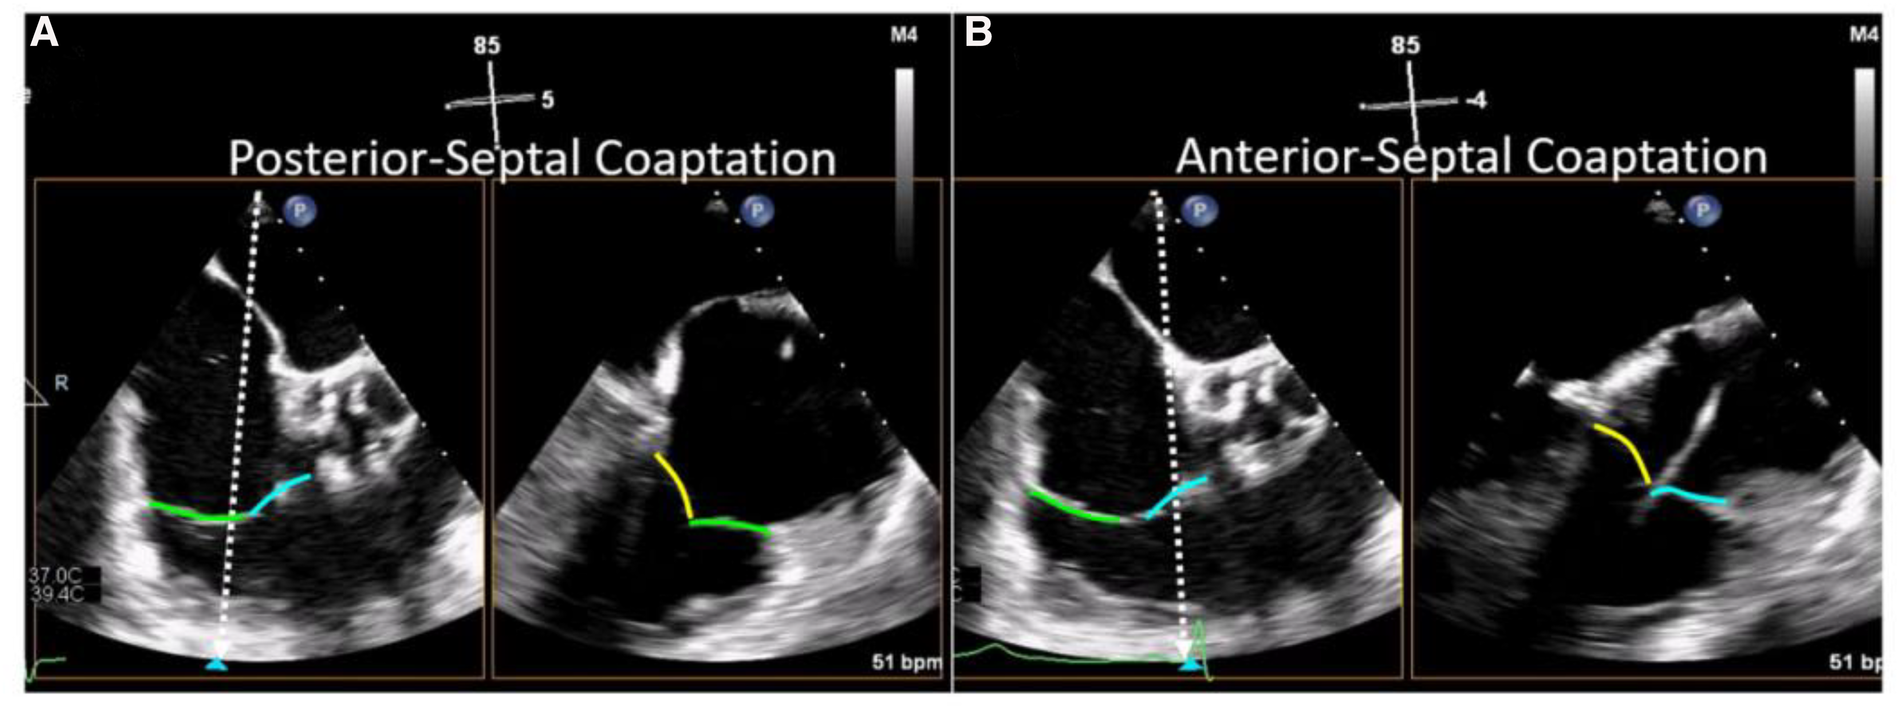

Evaluation of TV morphology and leaflet assessment is crucial to inform transcatheter device selection and should be systemically evaluated in all pre-procedural TEE examinations. A useful technique for leaflet assessment is biplane imaging from the mid or distal esophageal inflow-outflow view (also referred to as the “commissural view”) of the TV, which is typically acquired at 50–80 degrees of mechanical rotation. Using simultaneous biplane imaging, sweeping the orthogonal imaging plane from posterior (left side of sector) to anterior (right side of sector, near the aortic valve) visualizes the coaptation of the posterior-septal, then anterior-septal commissures, respectively (Figure 5). In this manner, specific leaflet abnormalities as well as coaptation gaps, can be localized and measured. Leaflet characteristics of relevance when planning TTVI include leaflet length, tethering, and coaptation defect width.

Figure 5

Biplane TEE Imaging of the tricuspid valve (reproduced with permission from (32)). The mid-esophageal right ventricular inflow-outflow view (at ∼50–80°) is considered the TV 'commissural' view with the anterior (blue line) and posterior (green line) leaflets imaged and the septal leaflet (yellow line) behind the imaging plane. Moving the orthogonal biplane cursor towards the posterior wall (A) images the posterior and septal leaflets. Moving the orthogonal biplane cursor towards the aorta (B) images the anterior leaflet near the aorta and the septal leaflet.